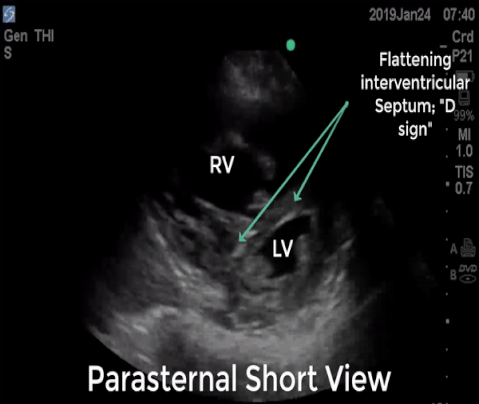

D Sign In Echo - Pasp can be estimated with echo by utilizing continuous wave (cw) .

Some consider gum to be candy. A bedside echo revealed evidence of rv strain (note the "d" shaped left ventricle). Additionally, evaluating for septal flattening, or the 'd' sign,. Vitamin d is important for maintaining a healthy body, primarily because it helps you fully maximize your body's absorption and utilization of calcium, an important mineral that we all need. Some candy that starts with the letter "d" include dum dums lollipops, dove chocolates, dots, daim bars, dairy milk by cadbury, dagoba organic chocolate, divinity, dip dabs, and dew drops. When paired with calcium, vitamin d helps regulat. Therese mead, do, emergency physician. Pasp can be estimated with echo by utilizing continuous wave (cw) .

A bedside echo revealed evidence of rv strain (note the "d" shaped left ventricle).